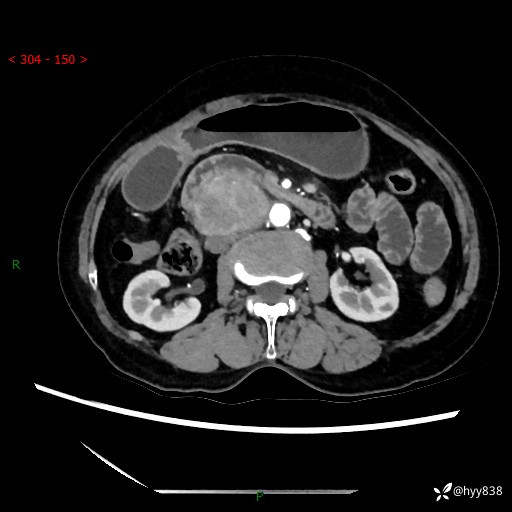

71岁/女,腹痛1月余。腹膜后肿物,间质瘤 VS 副节瘤 VS 平滑肌肉瘤---(有结果)

【患者信息】:71岁/女

【主诉】:腹痛1月余

【现病史及既往史】:患者于1月前无明显诱因出现右下腹部疼痛不适,呈阵发性隐痛,尚可耐受,放射至后背部及腰部疼痛,伴排便困难,不伴其它部位疼痛,无嗳气,无不洁饮食,无黑便,无恶心、呕吐、腹胀腹泻、呕血、发热、寒颤、厌油、黄疸,多次就诊于当地区太湖医院拍片示: 行抗炎等对症支持治疗,效果尚可。现患者上述不适症状明显进一步加重,为求进一步治疗遂来我院门诊就诊,门诊以“十二指肠肿瘤?”收住我科。 起病以来,精神、睡眠可,食欲可,大便异常、小便正常,体力、体重无明显下降。

【检查】:腹部CT增强扫描(外院CT平扫)